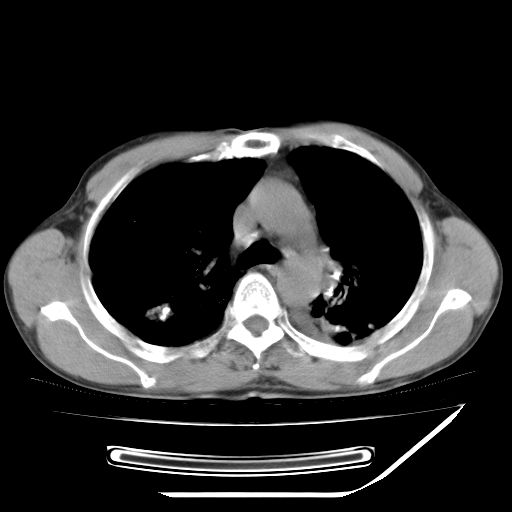

男,59岁,“结核性胸膜炎”30余年,胸部经常疼痛,多次x检查提示“肺部”炎症。腹部疼痛5日,b超提示:“肝内短管结石,余显示不清,建议进一步检查。”

两肺结核并右侧胸腔积液;脾脏、腹腔及腹膜后淋巴结结核[陈旧性];肝内胆管结石

胸部腹部都是结核(双肺。纵隔淋巴结,肝脏,脾脏,肠系膜)

两肺结核并右侧胸腔积液;脾脏、腹腔及腹膜后淋巴结结核[陈旧性];肝内胆管结石。直肠息肉?